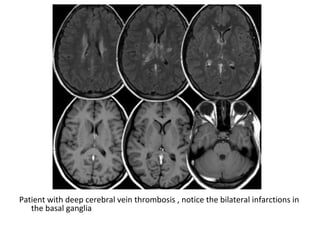

Thrombosis of deep cerebral veins

-The clinical presentation of thrombosis of the

deep cerebral venous system are severe

dysfunction of the diencephalon reflected by

coma and disturbances of eye movements and

pupillary reflexes , usually this results in a

poor outcome

-However , partial syndromes without a decrease in

the level of consciousness or brainstem signs

exist which may lead to initial misdiagnoses

-Deep cerebral venous system thrombosis is an

underdiagnosed condition when symptoms are

mild and should be suspected if the patient is a

young woman , if the lesions are within the basal

ganglia or thalamus and especially if they are

bilateral

Patient with deep cerebral vein thrombosis , notice the bilateral infarctions in

the basal ganglia